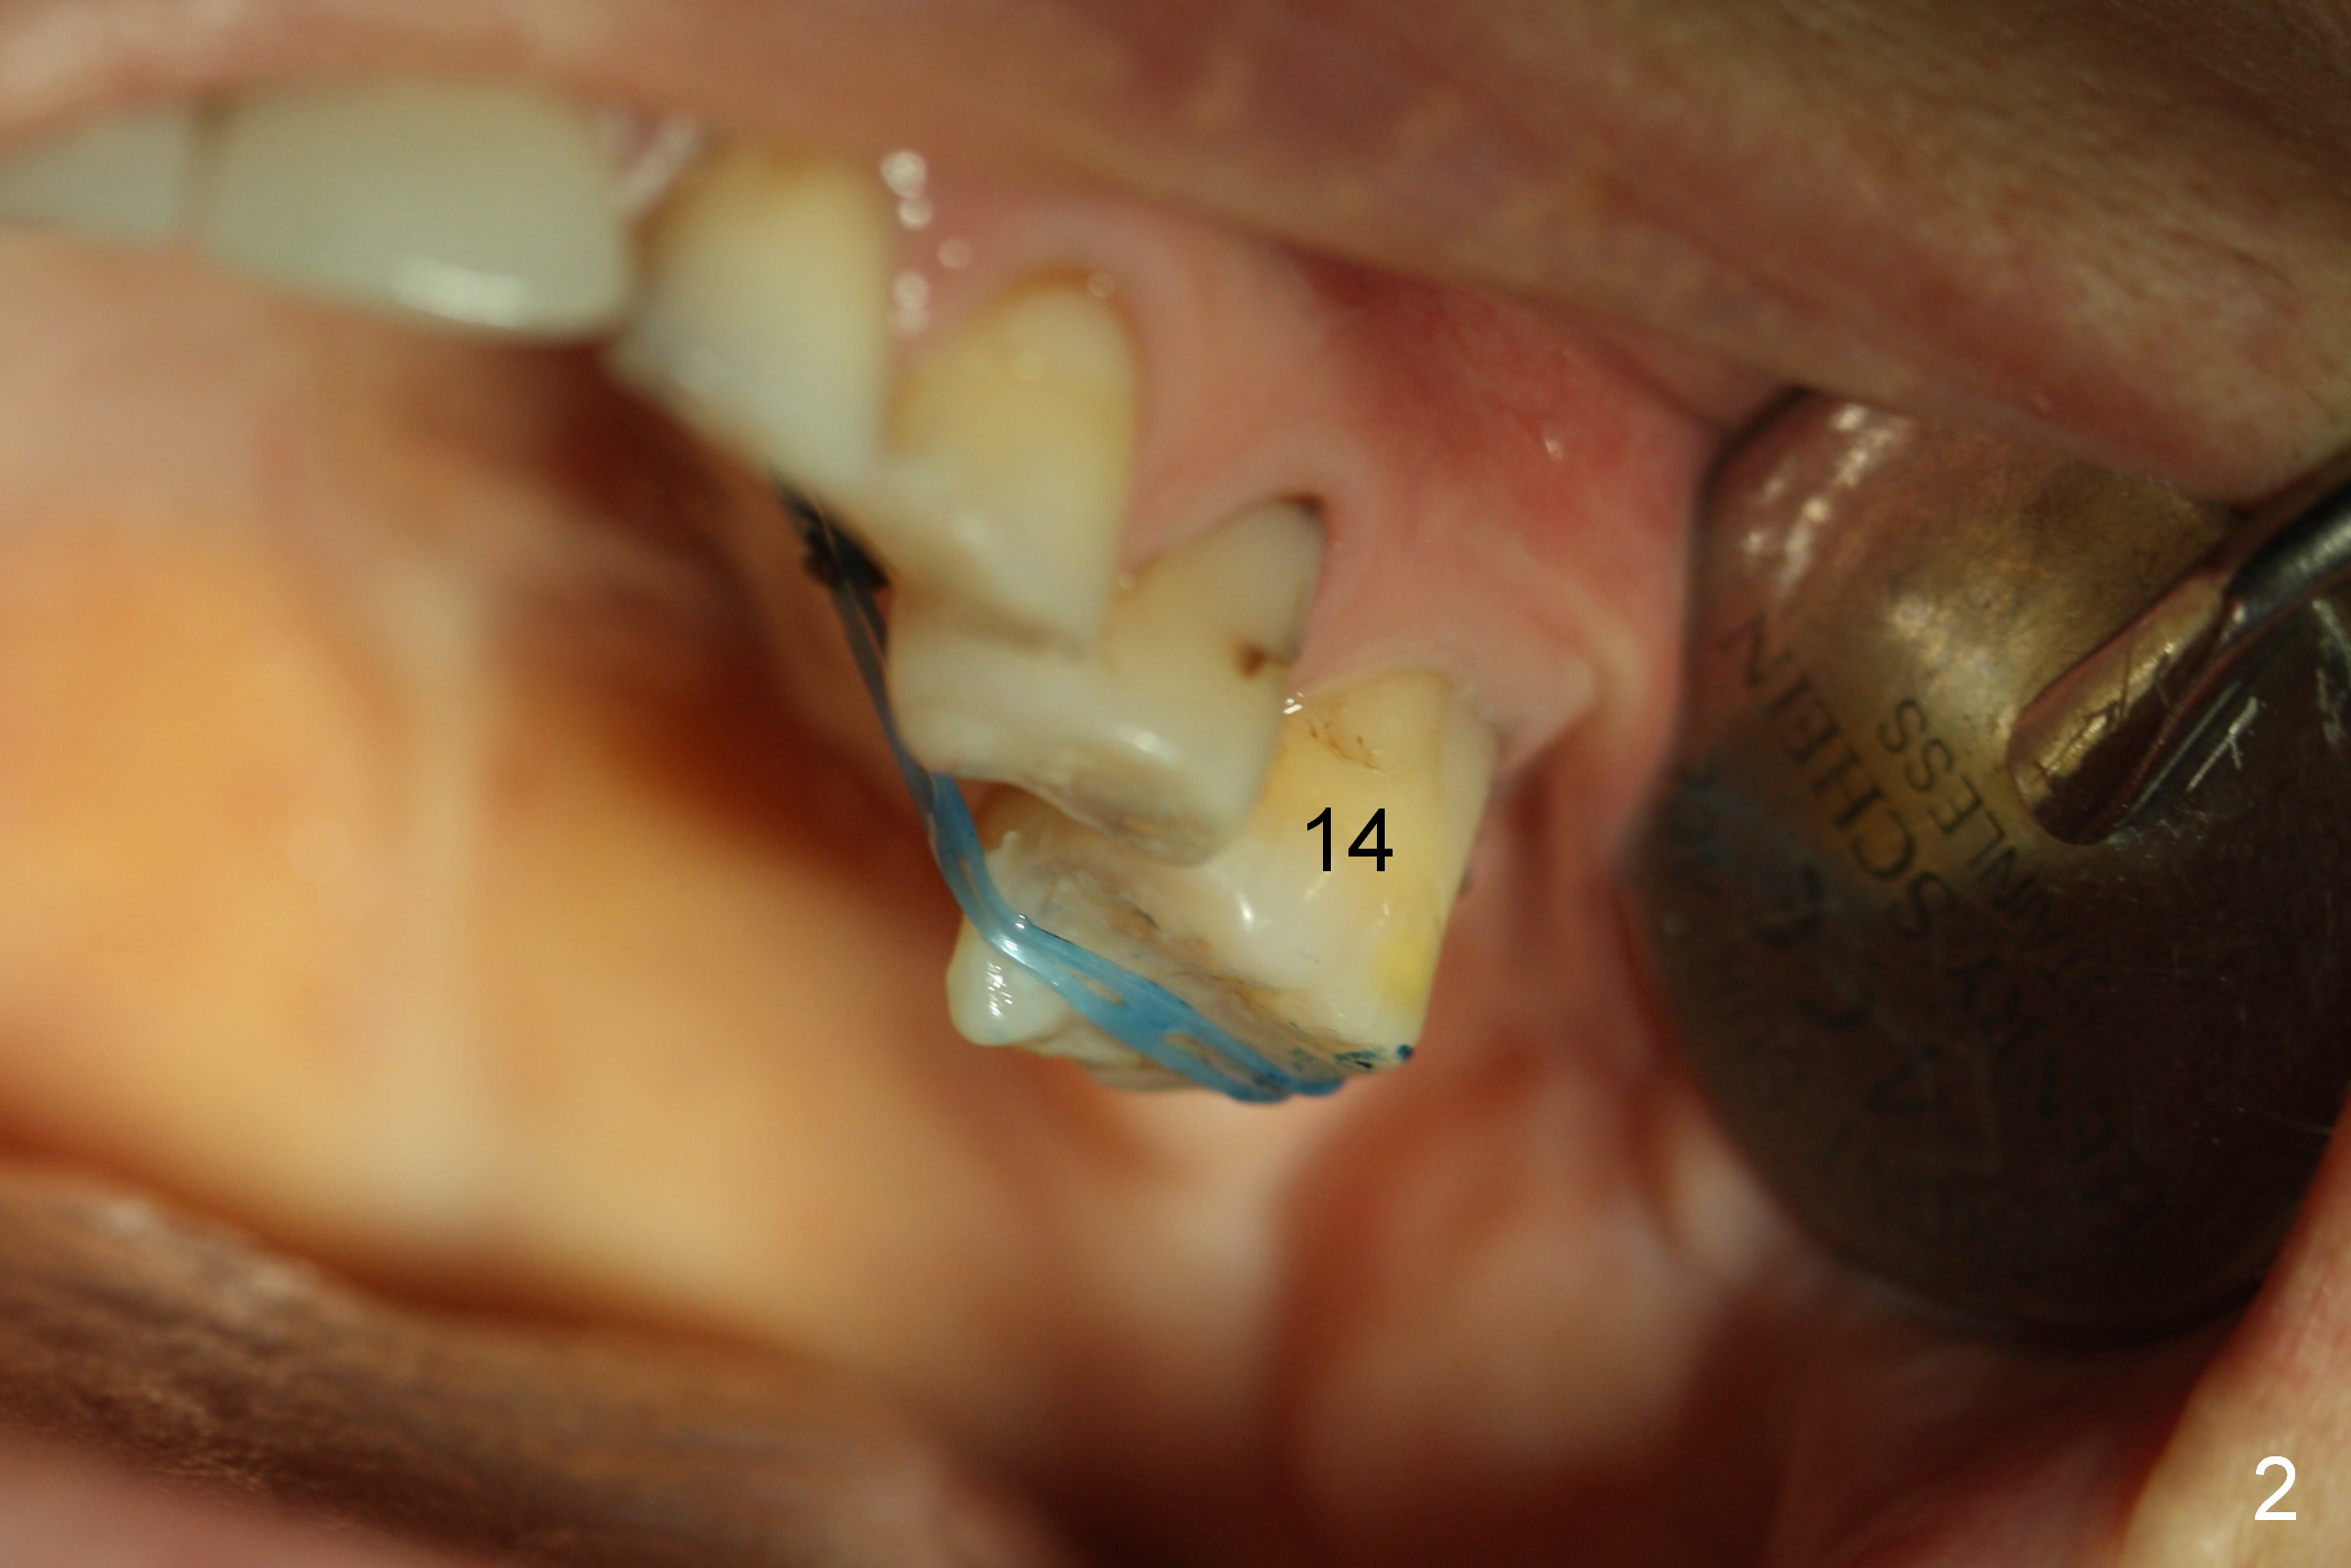

A 50-year-old lady had implant crown prep on 02/02/2015.  The intrusion of the opposing tooth was terminated (removing power chain).  She returned for crown cementation today (02/27/2015).  The temporary crown was broken for an unknown period of time.  When a Zirconium crown is seated at the site of #19, the rest of occlusion is off (Fig.1).  The contact with the neighboring teeth is within normal limit.

It appears that the opposing tooth is re-supraerupted.  Power chain of 4 is re-installed.  The crown is temporarily cemented.  Is there any other reason for the bite problem?  What can we do, especially what can we do to prevent crown cracking?